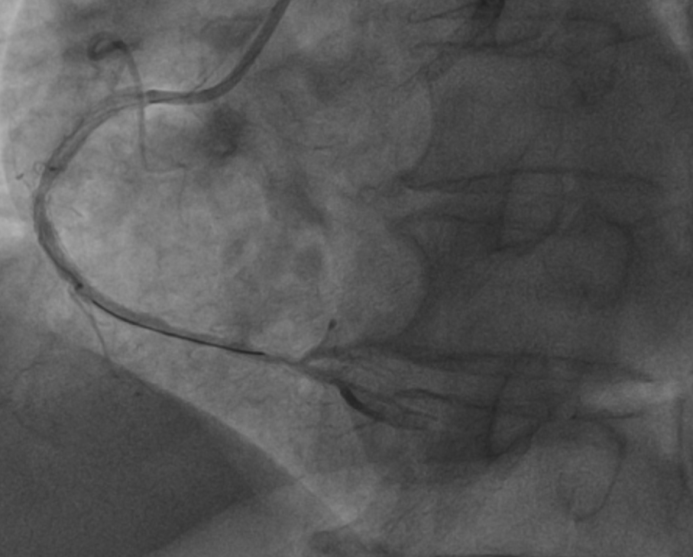

再处理RCA,王乂就从容了很多:RCA两支架间次全闭塞,送2.0*15mm球囊至远端病变处以12atm预扩,造影可见残狭减轻,PD近段90%狭窄,2.0*15mm球囊12atm扩张PD近段,造影血流减慢,冠脉应用替罗非班15ml、尼可地尔400μg后血流TIMI3级。再送3.0*14mm支架至RCAp病变处以18atm扩释,前向血流TIMI3级。(图4)

图4.右冠术后状况